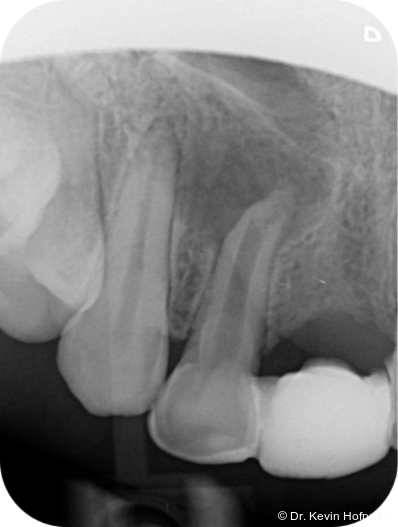

Klinisch zeigten sich die Zähne 12 und 13 karies- und füllungsfrei. Zahn 12 reagierte nicht auf Sensibilitätstests und war leicht perkussionsempfindlich. Zahn 13 reagierte unauffällig. Radiologisch zeigte sich eine ausgedehnte apikale Aufhellung am Zahn 12 sowie eine Hartgewebsformation im apikalen Kanallumen (Abb. 1–2d).

Geplant wurde eine Wurzelkanalbehandlung an Zahn 12. Die zunächst vorgesehene Zystektomie mit Wurzelspitzenresektion wurde zurückgestellt, um die Heilungstendenz nach orthograder Therapie zu beurteilen und einen chirurgischen Eingriff möglichst zu vermeiden.